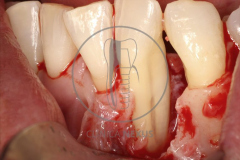

Tratamiento de defectos periodontales infraóseos en sector antero-inferior empleando gel de amelogeninas (Emdogain®) en combinación con un aloinjerto óseo (Biobank®). Paciente de 64 años, sin problemas médicos de relevancia, que presenta una periodontitis leve generalizada, pero asociada a presencia de defectos óseos verticales profundos a nivel de los espacios interdentales entre los caninos y los incisivos laterales inferiores. Tras la pertinente fase higiénica, se llevó a cabo una cirugía periodontal regenerativa, en la que, tras eliminar el cálculo subgingival (factor causal), se empleó una combinación de amelogeninas con un aloinjerto, para promover la regeneración tisular del periodonto perdido. Las imágenes clínicas y radiológicas, al año de seguimiento, reflejan un resultado terapéutico óptimo, con regeneración completa del tejido periodontal y mejora del pronóstico de los dientes involucrados.